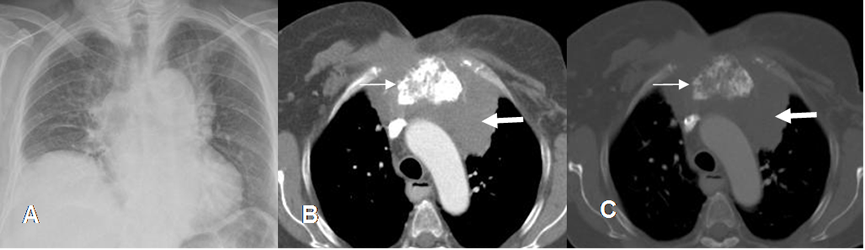

Fig 47. Condrosarcoma.

A: Rx PA. Ensanchamiento mediastinal. Hay elevación del hemidiafragma derecho.

B: TAC axial en ventana de tejido y C: TAC axial en ventana ósea. Engrosamiento y alteración en la configuración del esternón por proceso neoplásico, con matriz de tipo condroide. (Flechas delgadas). Adicionalmente hay masa de tejidos blandos que ocupa el mediastino. (Flechas gruesas).